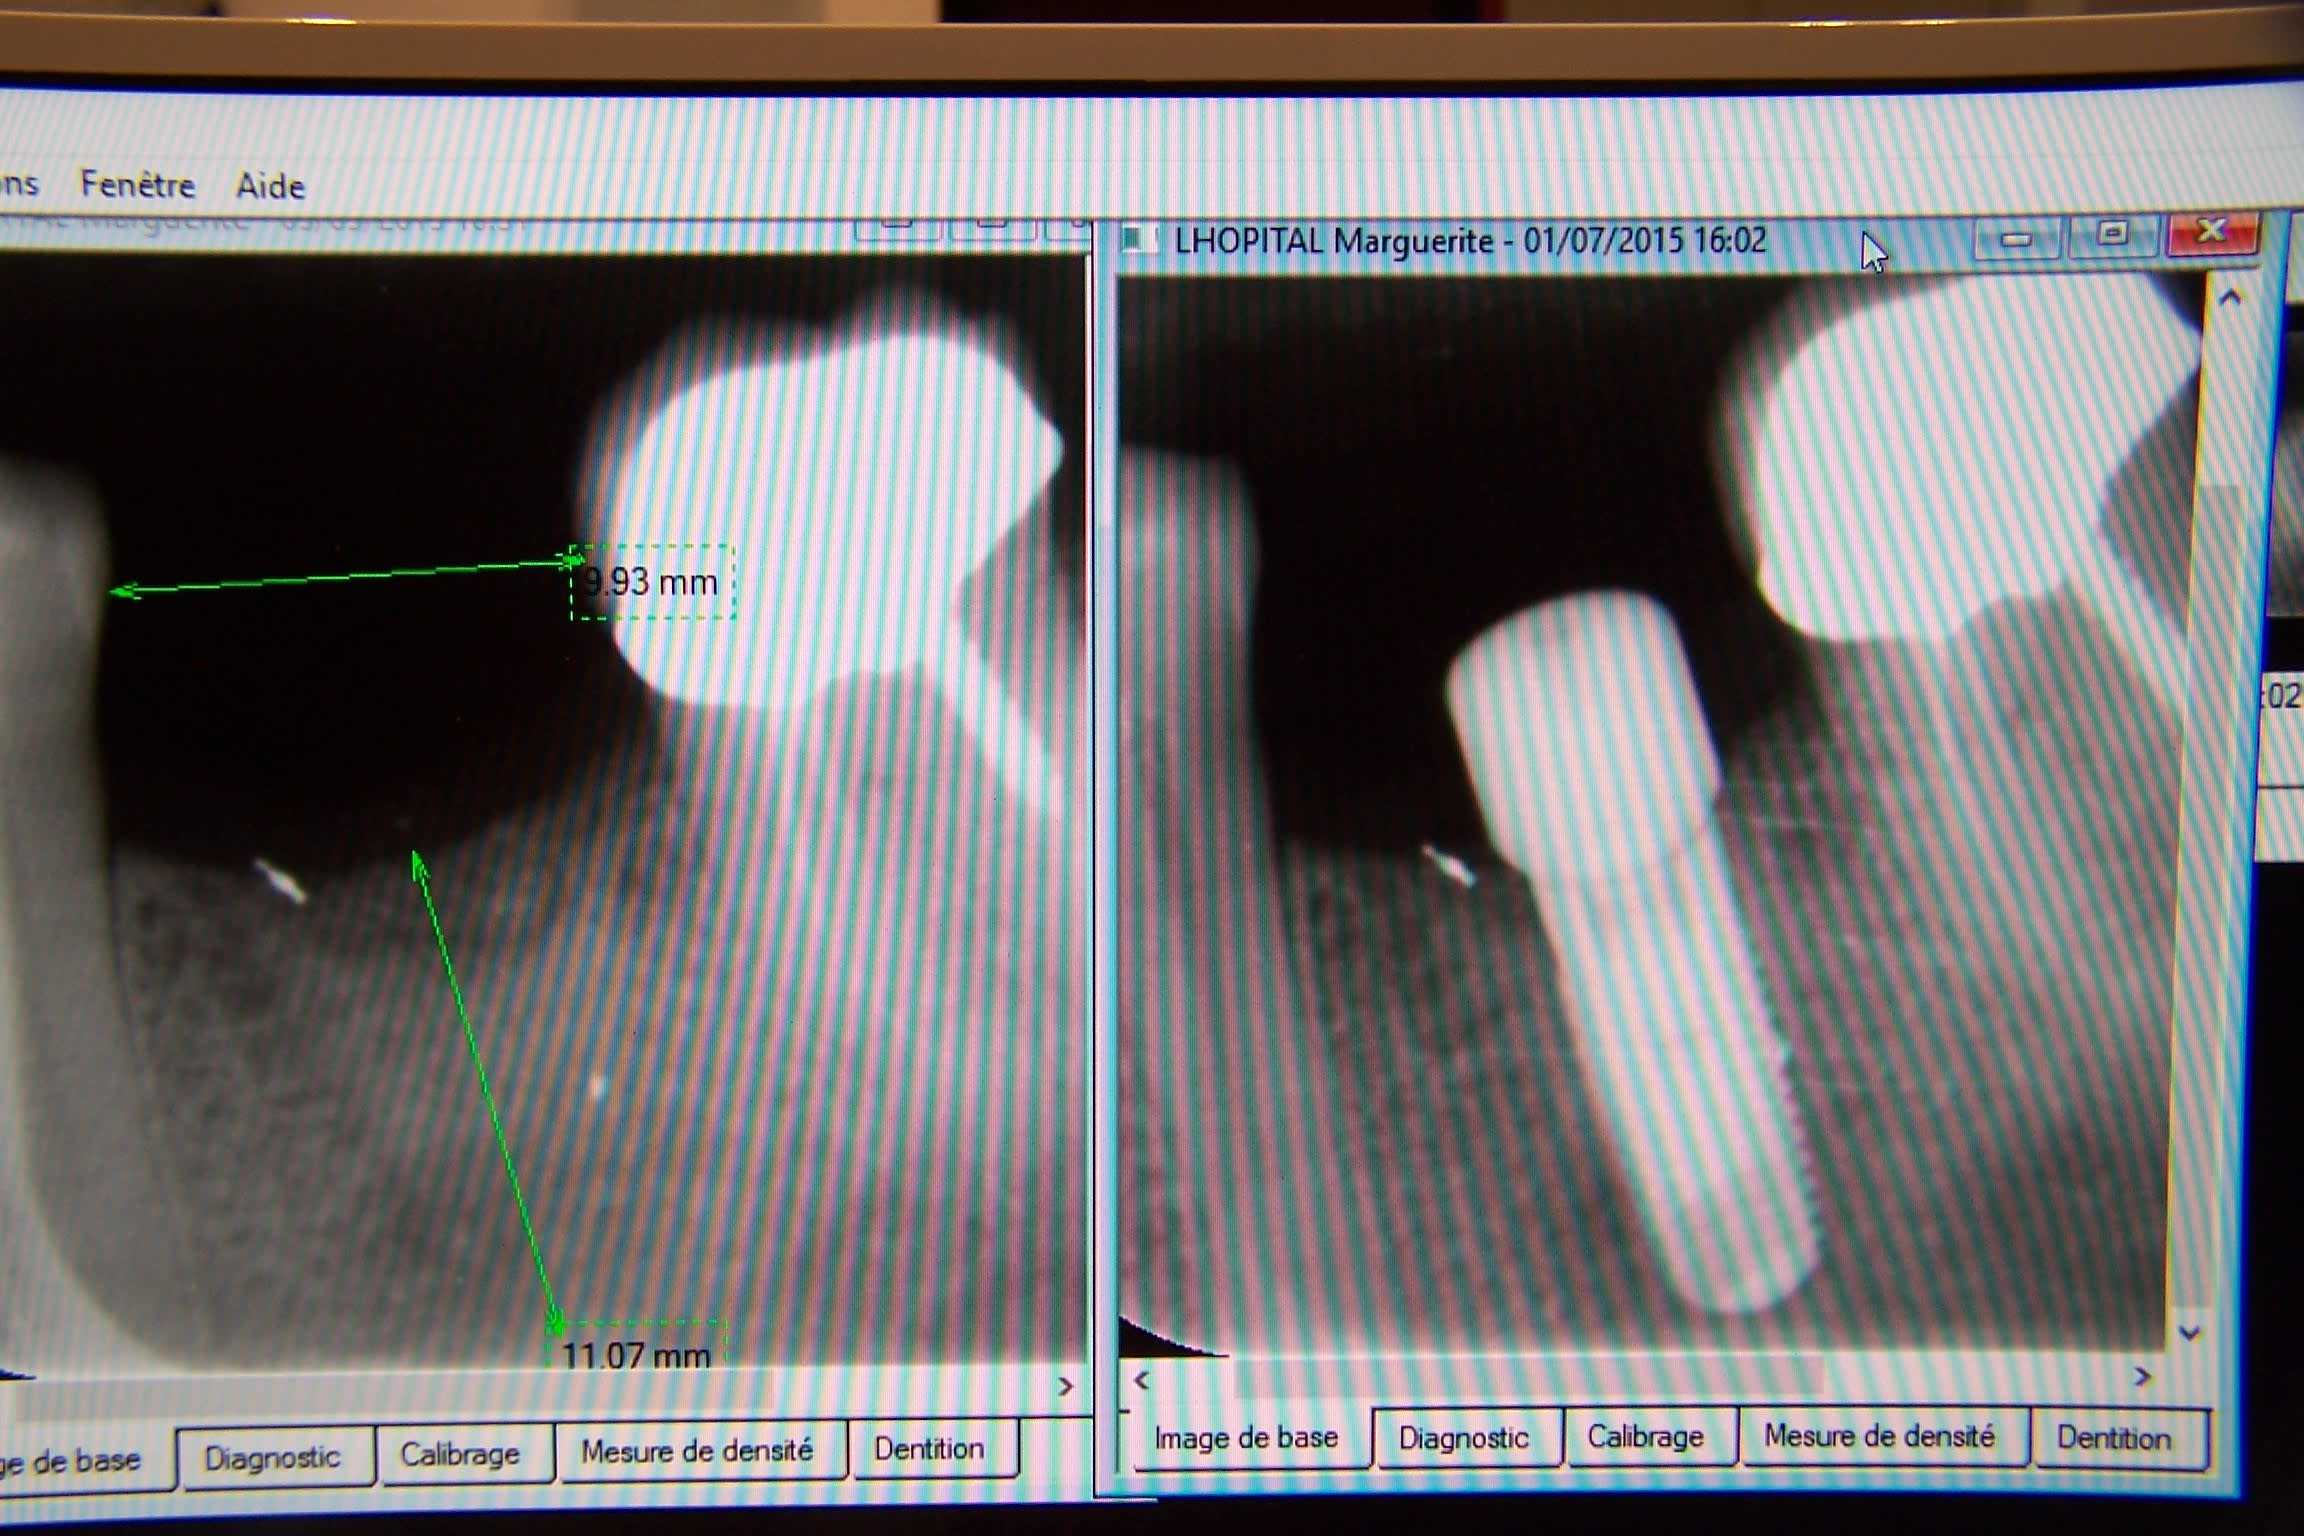

Un cas un peu extreme :

Non pas de sinus, que des alvéoles avec une paroi plus ou moins defectueuse. Quand tu reviens pour forer la sensation est bonne, il y a quelques petites particules blanches uniquement en surface.

Dans le cas que j'ai montré j'avais mis qu'une dose de 0,15 ( = une seringue), sur la radio de controle ça faisait un peu juste, mais finalement ça a bien marché.